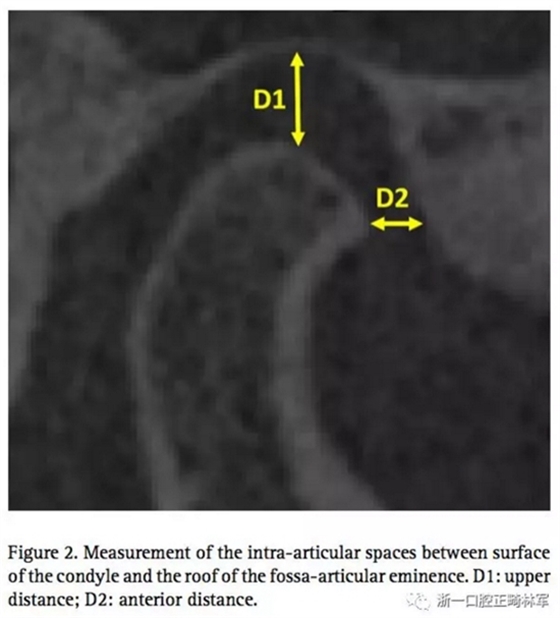

通過這個(gè)正常TMJ關(guān)節(jié),設(shè)計(jì)其他三個(gè)模型,包括有無??墊的,有無關(guān)節(jié)盤前移位的。因此,志愿者需要佩戴??墊進(jìn)行CT掃描,去分析上頜距離D1和關(guān)節(jié)間隙(關(guān)節(jié)面和關(guān)節(jié)窩之間)上部分距離D1和前部分距離D2。(圖2)可以發(fā)現(xiàn),因?yàn)槟パ篱g2mm的??墊,前關(guān)節(jié)腔有少量的增長(zhǎng),還有髁突輕微的旋轉(zhuǎn)。